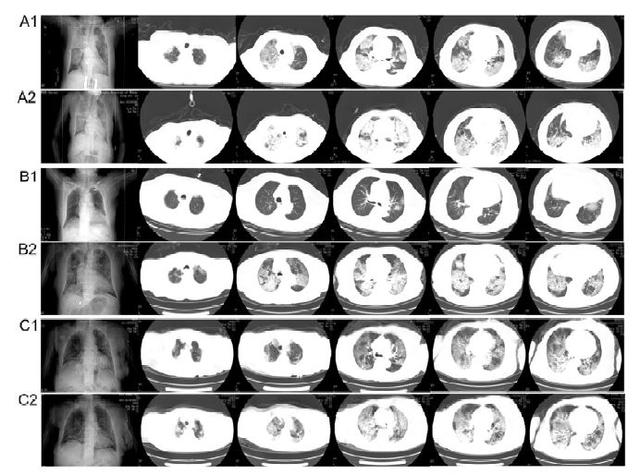

胸部CT扫描显示,患者肺部病变在疾病晚期(A2、B2、C2)较早期(A1、B1、C1)更严重(来源:medRxiv)